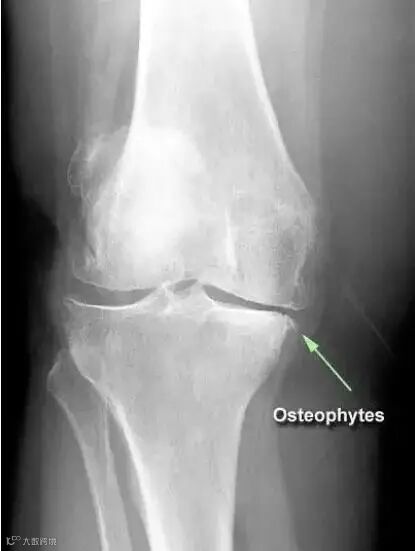

比如说,膝关节骨质增生,是因为膝关节骨性关节炎(Osteoarthritis)或膝关节外伤后的创伤性关节炎(Traumatic arthritis)导致关节病变、损伤以后,关节为了建立新的稳定,继发出现了骨质增生。